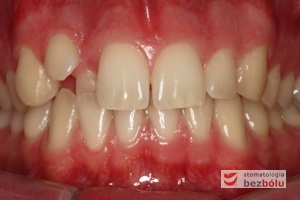

Młody 28-letni, pogodny, stale uśmiechnięty pacjent zgłosił się celem korekcji wad zębowych ograniczających pełną ekspresję uśmiechu. Głównym problemem był dodatkowy siekacz boczny (dwójka) po stronie prawej w łuku górnym. Dodatkowy ząb spowodował stłoczenia pozostałych zębów w łuku górnym oraz przesunięcie linii pośrodkowej. Obliczenia dostępnego miejsca dla siekacza bocznego wpłynęły na wybór zęba przeznaczonego do ekstrakcji. Usunięto dwójkę ustawioną dowargowo, zaś jej „siostrę bliźniaczkę” skierowaną w stronę podniebienia wprowadzono do łuku zębowego w drodze leczenia ortodontycznego. Problemem było szczelne zamknięcie szpary poekstrakcyjnej z powodu nadmiaru miejsca w kości. Wyrównano linię pośrodkową. Leczenie przeprowadzono jednym łukiem ortodontycznym górnym, dolny łuk zębowy nie wymagał założenia aparatu. Po zdjęciu zamków korekcję detali przeprowadzono z użyciem pozycjonera wykonanego w technice termoformingu. Stabilizację efektów leczenia zapewnił stały retainer klejony do powierzchni podniebiennych siekaczy górnych.

Leczenie ortodontyczne: planowanie i aktywna faza leczenia, leczenie retencyjne – lekarz stomatolog Magdalena Żywicka i lekarz stomatolog Marta Pakuła